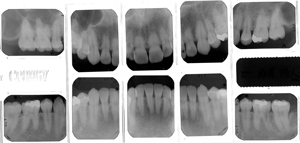

STEP03検査②【レントゲン撮影】

さらに的確な診断を行うためにレントゲンを撮影します。

デジタルレントゲン撮影はX線の被曝量が従来のレントゲンの1/4~1/10程度になりますのでより安心してレントゲン撮影をすることができます。 -